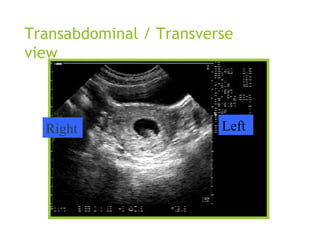

Transabdominal / Transverse

view

Right Left